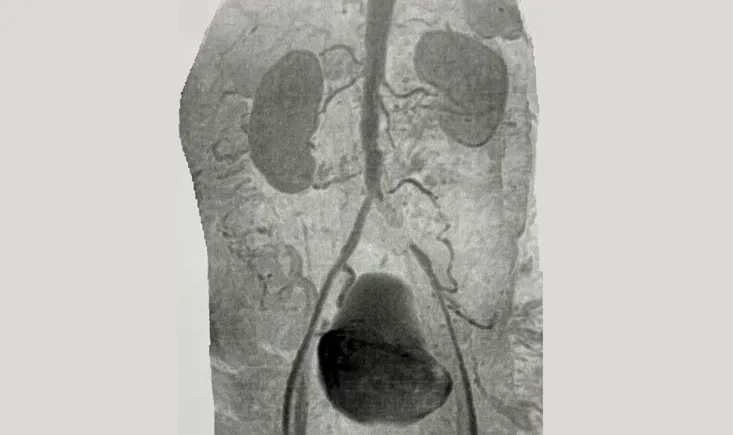

A 65-year-old male with multiple comorbidities presents with a 58 mm thoracic aortic aneurysm and a severel…